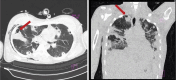

Patient concerns: A 31-year-old woman from California, United States (US), was admitted to the emergency room with a history of 2 days of fever and severe throbbing pain in the left cervical region. Thorax and neck CT tomography revealed confluent cavities suggestive of septic embolism in the lungs and a filiform thrombus in the lumen of the left internal jugular vein, with moderate swelling of the soft and muscular tissues. Methicillin-resistant Staphylococcus aureus (MRSA) was isolated from the blood culture.

Diagnosis: The thrombus in the internal jugular vein associated with cellulitis in the neck and multiple cavitary lesions in the lungs support the diagnosis of LLS caused by MRSA with septic embolization.